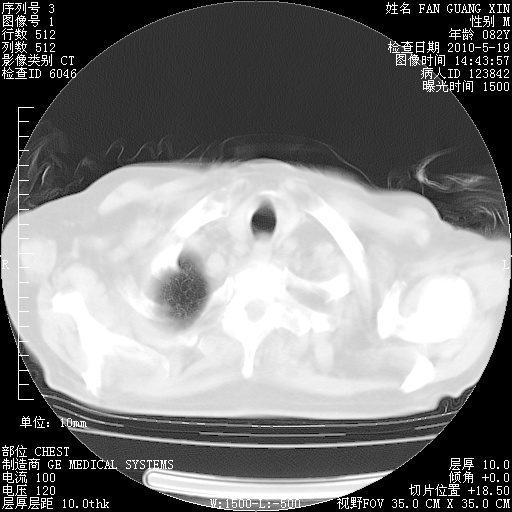

复查肺部CT,明显好转。为什么发热呢?

治疗3周后的肺部CT